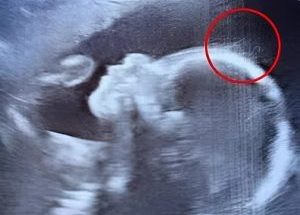

Doctors couldn’t believe what they saw during the ultrasound. But when the baby girl was born, her charm, strength, and story touched hearts around the world in the most unexpected way.

July 22, 2025 - by Ten11 - Leave a Comment

When 29-year-old Emily Foster from Kent, England, walked into the hospital for her 20-week pregnancy scan, she expected the usual routine: a grainy image, a few measurements, and maybe a …